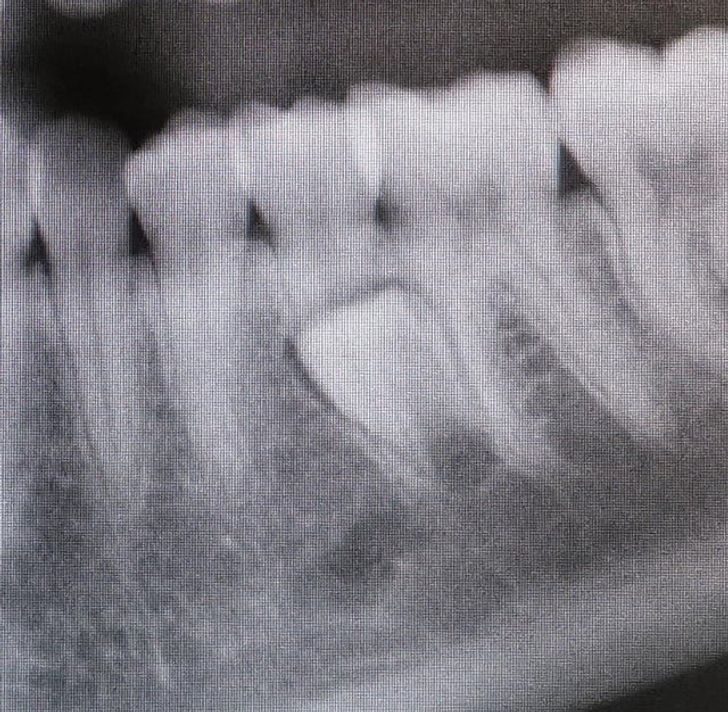

«Ходил сегодня к стоматологу. У меня давно есть все коренные зубы, но, оказалось, существует еще и „бонусный“ зуб»

У людей с ключично-черепной дисплазией похожая картина: только дополнительных зубов очень много